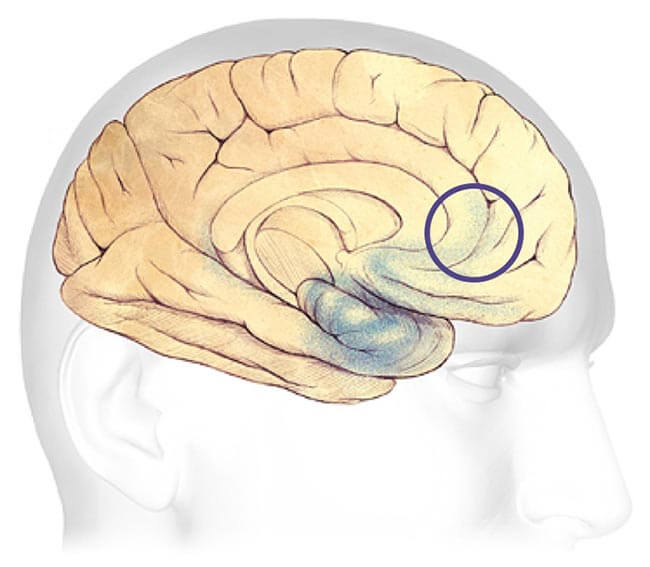

Progression Through the Brain

Plaques and tangles (shown in the blue-shaded areas) tend to spread through the cortex in a predictable pattern as Alzheimer's disease progresses. The rate of progression varies greatly. On average, a person with Alzheimer's lives four to eight years after diagnosis, but can live as long as 20 years, depending on other factors. The course of the disease depends in part on age at diagnosis and whether a person has other health conditions.

Mild to moderate Alzheimer's stages - generally last from 2 - 10 years.

Mild to Moderate Alzheimer's

In mild to moderate stages, brain regions important in memory and thinking and planning develop more plaques and tangles than were present in early stages. As a result, individuals develop problems with memory or thinking serious enough to interfere with work or social life. They may also get confused and have trouble handling money, expressing themselves and organizing their thoughts. Many people with Alzheimer's are first diagnosed in these stages.

As Alzheimer's progresses, individuals may experience changes in personality and behavior and have trouble recognizing friends and family members.

Plaques and tangles also spread to areas involved in:

Speaking and Understanding Speech

Your sense of where your body is in relation to objects around you